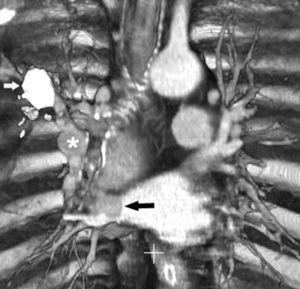

Fig. 11.--N2. (A) Corte axial de tomografía computarizada (TC) con contraste. Nódulo heterogéneo en el segmento 6 del lóbulo inferior derecho con infiltración de la vena pulmonar inferior (flecha). (B) En la reconstrucción de volumen se ponen de manifiesto la infiltración tumoral de la vena pulmonar (flecha negra), la adenopatía hiliar (asterisco) y una adenopatía calcificada lobar superior derecha (flecha blanca).